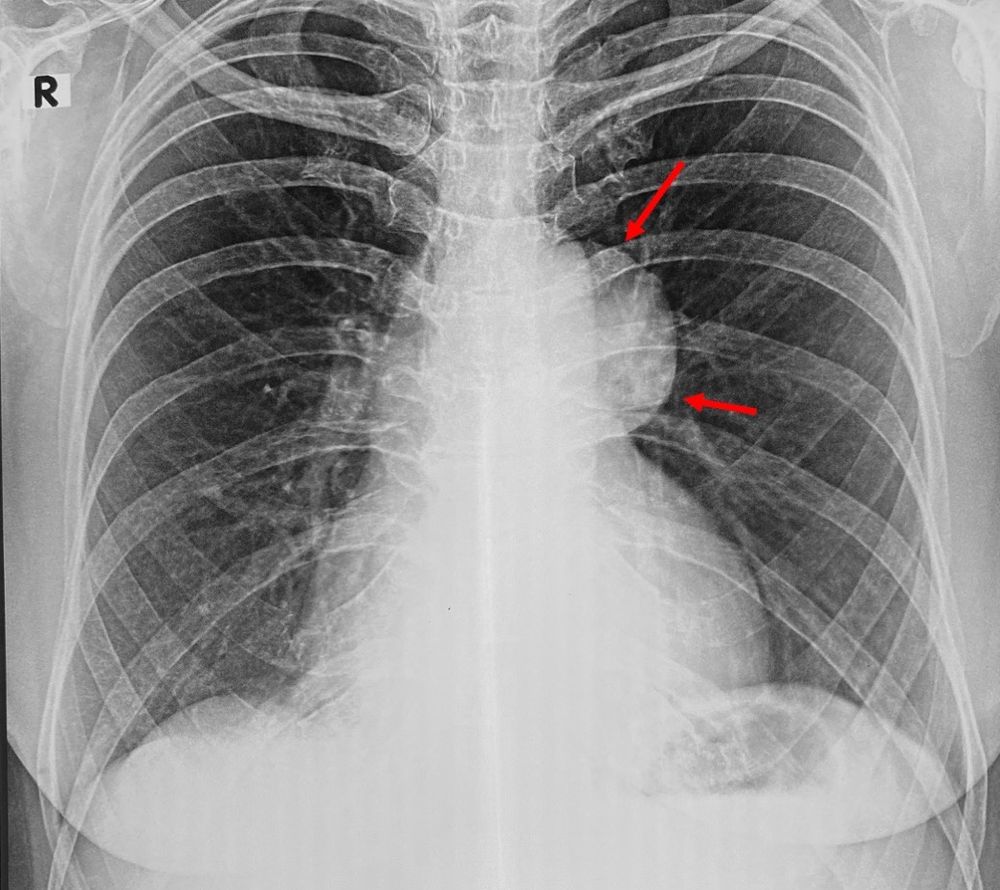

Huge Congenital Thymic Cyst with Microscopic Thymoma Thymic Cyst Vs Thymoma They are usually asymptomatic and mostly occur in. Although thymic cysts are often reported,. However, the data from which we can draw this. Computed tomography is the imaging modality of choice for evaluating thymoma and can help distinguish thymoma from other anterior mediastinal. Cystic changes in thymomas are differentiated by the lack of epithelium on the cyst wall. Lymphoid follicles. Thymic Cyst Vs Thymoma.